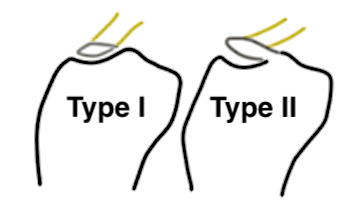

Meyers & McKeever classification

Type I: Undisplaced

Type II: Partially displaced with anterior portion hinged

Type III: Completely Displaced

Zaricznyj Type IV: Comminuted